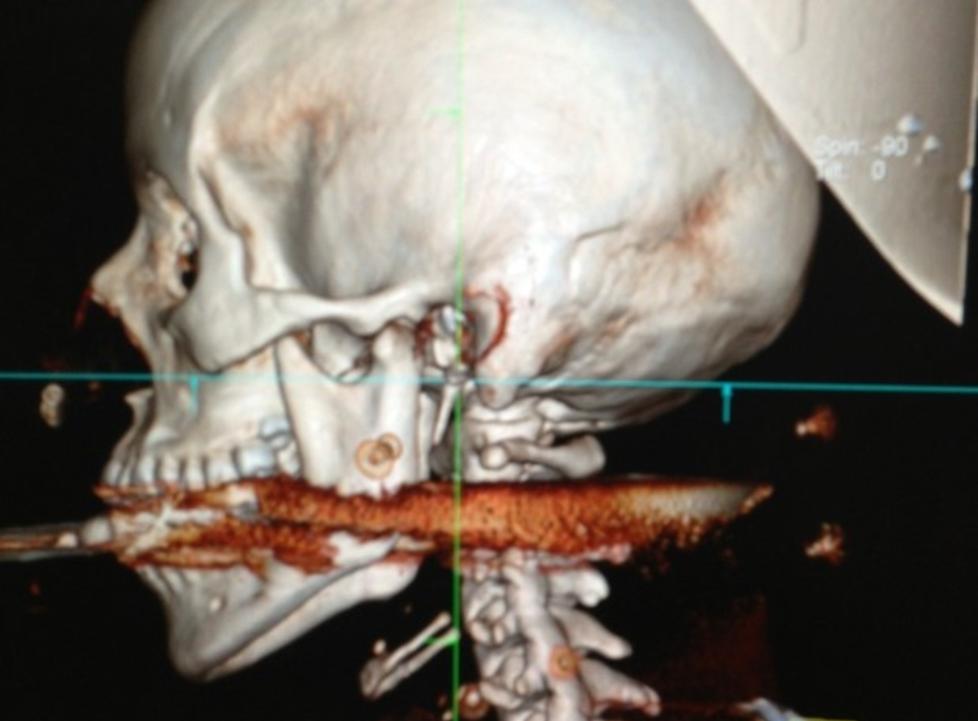

Harpunen gikk ifølge nyhetsbyrået AP gjennom kvinnens kjeve og inn i ryggraden. Men legene er optimistiske og tror kvinnen vil komme fra hendelsen uten alvorlige varige mén.

Sykehuset har frigitt et bilde fra operasjonen, som er publisert i flere brasilianske og internasjonale medier.